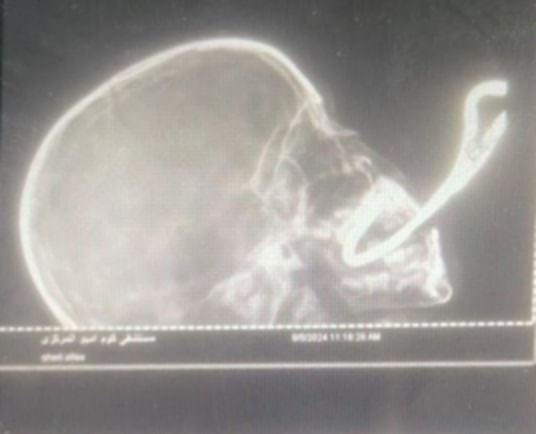

وقال الدكتور أحمد قناوي رئيس قسم جراحة التجميل إن سيخا حديدا صدئا ملتويا تعلق بسقف الحلق في قاعدة الجمجمة وأجريت العملية من فريق طبي متميز.

استخراج الجسم الحاد من فم الطفلة

وأضاف الدكتور أحمد قناوي رئيس قسم جراحة التجميل أنه قام فريق التخدير بتركيب أنبوب تنفس حنجري وتم التعامل مع الجسم الحاد لاستخراجه من داخل بلعوم الطفلة ذات الثلاث سنوات بواسطة فريق قسم جراحة التجميل والإصلاح وجراحة الوجه والفكين دون التسبب في اي مضاعفات أخرى او تهتك بالأنسجة الداخلية او خرق للأوعية الدموية أو الأعصاب الدماغية.